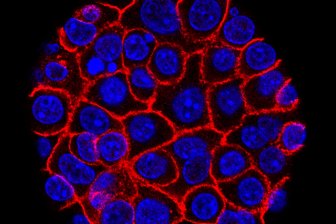

U of A researchers discover new drug that could revolutionize cancer treatmentThe newly discovered drug works by preventing cancer cells from repairing their own DNA during treatment.ScienceNov 19, 2019